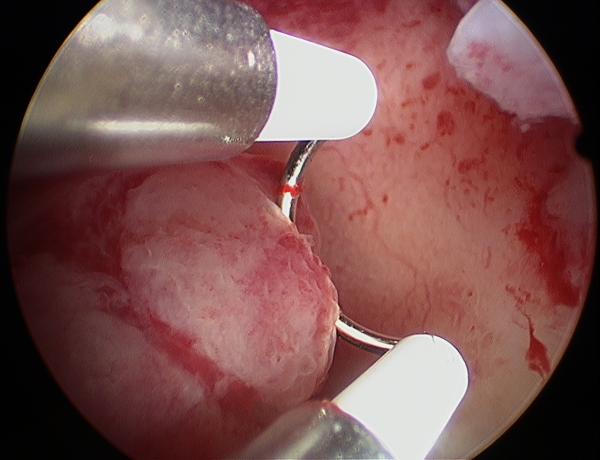

- هیستروسکوپ برای حذف چسبندگی داخل رحمی مورد استفاده قرار می گیرد، اما هنوز هم باعث سقط جنین می شود. لاپاروسکوپی ( عمل لاپاراسکوپی رحم و لاپاراسکوپی تخمدان را بهتر بشناسیم) نیز برای بررسی سطح رحم و جلوگیری از انجام آن به وسیله هیستروسکوپی انجام می شود. برای حذف بافت زخم، پزشک متخصص ممکن است به تجزیه چسبندگی هیستروسکوپی بپردازد. این یک عمل سرپایی است که در آن دکتر با استفاده از هیستروسکوپ به مشاهده لایه رحم و آشفتگی بافت زخم می پردازد. اگر بافت زخم پراکنده و نازک باشد، ممکن است پزشک بتواند از خود هیستروسکوپ استفاده کند تا از بین برود. اگر عمیق باشد، قیچی جراحی می تواند مورد استفاده قرار گیرد.